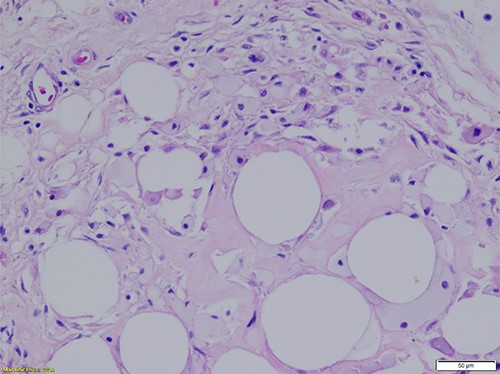

Histopathologic evaluation of representative hematoxylin and eosin (H&E)-stained sections from each specimen were similar and showed mature adipocytes of typically uniform size with foci of degeneration of fat necrosis. Adipocytes did show varying sizes in these regions of necrosis and degeneration. The tumors exhibited the typical fibrous septal vascularity of mature, benign lipomas. Rarely, focal microcalcifications are seen in areas of fat necrosis with degenerative adipocyte changes (Figs 1 and 2).

Region of fat necrosis within the benign lipoma. Scattered inflammation and focal degenerative adipocyte changes are seen along with rare microcalcifications (H&E-stained section, ×200 total magnification: ×20 objective with ×10 ocular lens) (Courtesy Karl Biesemier, MD. Pathology Consultants of Central Virginia, Lynchburg, VA).